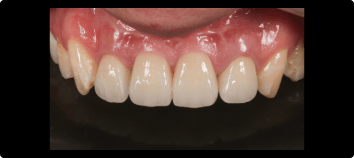

前歯のインプラントの症例

前歯を綺麗に治したい

BEFORE

AFTER

症例概要

年代・性別

50歳代 女性

主訴

治療内容

上顎両側1番インプラント、上顎両側2番セラミッククラウン、根管治療

治療期間

4ヶ月

治療のリスク

骨が少ない場合や膿の大きさが大きい場合は同時にできない場合があります。

治療費用

1,210,000円(税込)